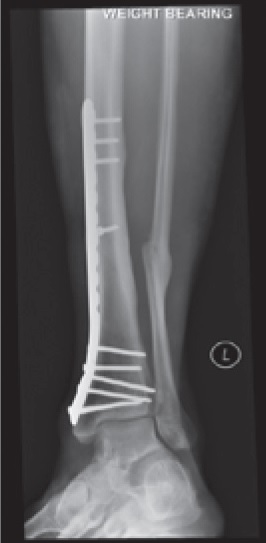

How will my bone be fixed?

Open fractures almost always need surgery to put the bone back and hold it there while it heals. This can be done in a number of ways. Examples are shown below. Your surgeon will discuss with you what he/she feels is in your best interest.

What is internal fixation?

Internal fixation is when either a rod inside the bone or plates on the surface of the bone are fixed to the bone with screws. These generally stay in forever but can be removed if there are any problems, but this is very uncommon.